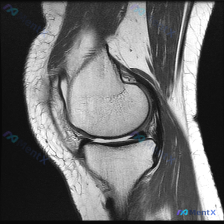

看到这个很有代表性的读片病例,整理出来和大家分享,这个临床-影像不匹配的情况其实临床工作中挺常见的。 病例基本信息 本次分析基于一张膝关节矢状位T1加权磁共振图像,临床提示存在「chondral abnormality(软骨异常)」,无其他病史、体征或检验结果提供。 影像基本观察(单张T1序列) 先...

今天遇到一个挺典型的临床情况,整理出来和大家聊聊:核心问题是临床观察提示「软骨异常」,但我们拿到的单幅膝关节MRI冠状位T2加权像分析却全是阴性结果,一起来理理思路。 先给大家放完整影像信息: 1. 整体结构对位:股骨远端胫骨近端对位正常,无骨折错位 2. 骨髓信号:股骨髁、胫骨平台骨髓信号大致均匀...

看到一个有意思的影像读片问题,整理了完整的分析思路分享给大家。 病例/影像基本信息 这是一张单幅膝关节矢状位T1加权MRI影像,问题是观察图像中是否存在软骨异常。 影像本身特点:图像有明显噪声(颗粒感重),对比度一般,解剖结构轮廓可辨认,但精细细节分辨率受限,属于质量不佳的单幅影像。 系统性影像观察...

遇到一个挺典型的读片问题,整理出来和大家分享一下思路: 病例背景 临床关注点:怀疑膝关节软骨异常,提供单张膝关节MRI矢状位T1加权像(T1WI)读片 影像基础评估结果 先把影像上能看到的情况理清楚: 1. 骨性结构:股骨远端、胫骨近端皮质连续,没有骨折;骨髓信号是正常脂肪骨髓的灰白色信号,没有局灶...

刚梳理完一份膝关节MRI读片病例,核心问题是「这张图像中可视觉识别的潜在异常是什么?」,标准答案提示是软骨异常,不过整理完发现这个病例其实挺值得讨论,分享一下完整分析思路。 病例影像基础信息 这是一张膝关节MRI冠状位影像,我们先整理客观观察到的所有征象: 1. 骨骼结构:股骨远端、胫骨平台骨皮质连...